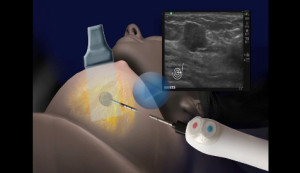

I didn’t even take my shoes off for the procedure! Just my bra and blouse before donning another one of the Women’s Center’s heated fluffy robes and walking across the hall to where Dr. Tomkovich was making his last minute preparations for killing my cancer. Everything was ready, the technician was at the ultra sound machine, the Ice-Cure console with its interface, multiple control options, push buttons, touch screen and foot pedal was all in readiness for Dr. Tomkovich’s experienced and knowledgeable use, and I was excited. Dr. Tomkovich, by now used to my interminable questions and curiosity, explained that it is actually the needle, not my body, that receives the liquid nitrogen; the closed end needle that would be inserted directly into the center of the tumor would be frozen by the liquid nitrogen to approximately -150 degrees centigrade and would last seven minutes. The time, he explained, was based on his calculations of the size of the tumor and the target tissue he wanted to kill with it. He told me he would create an ‘ice ball’ around the tumor to be sure yet any possibly unseen cancer in the surrounding areas was also frozen. Basically, I would see on the ultra sound about a 2 inch ice cube made from my breast tissue.

I am sure there are lots of precise technical issues in place, from judging the proper size needle to use, the number of minutes the tumor would be frozen, and other facts Dr. Tomkovich knows. I was just content to know he’d swab my breast with a local anesthetic…isn’t freezing a natural anesthetic?….insert a second needle with saline to ensure my skin didn’t get ‘frost-bitten’ from within and he had a steady hand and great eyesight to put that needle right smack dab in the middle of a tumor that had no business being in the middle of my breast. Besides, again at my request, he positioned me so I, too, could see this magic on the ultra sound screen!

There were precise timings, precision insertions, a lot of medical talk I didn’t understand, and intense interest among everyone in the room. I was swabbed, the needle inserted, and wonder of wonders…I could see a little ice ball building up inside me! No pain, no feeling of anything. Just pure sheer magic performed by an ultra competent and confident radiologist!